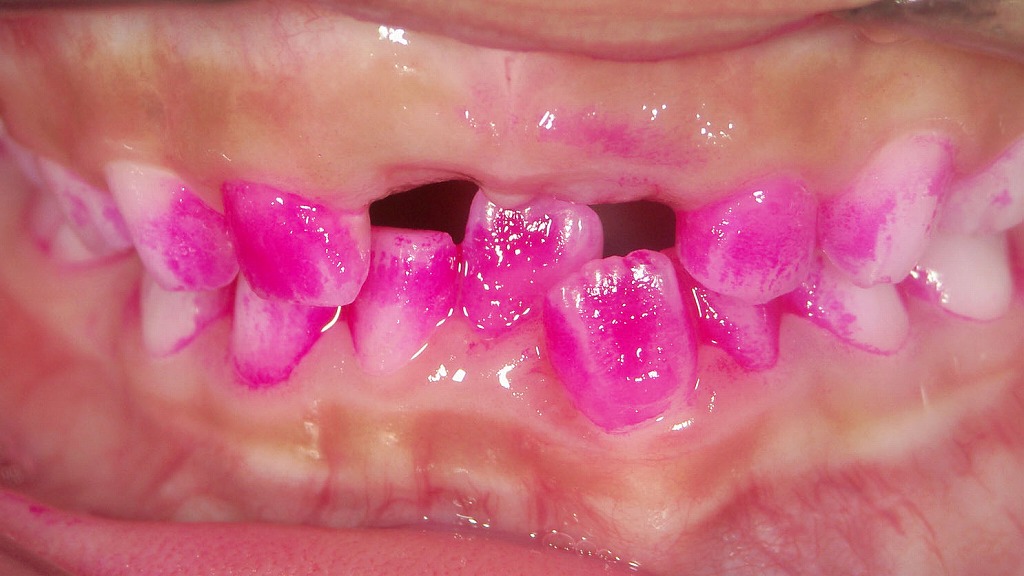

- 7.1.1. 🩷 ― 染め出しで分かる磨き残し ―

染め出しを行うと、歯と歯の間や歯ぐきの境目に磨き残しがはっきり現れます。

特に前歯の裏側や歯並びが重なっている部分は、毎日の歯磨きだけでは汚れが残りやすい場所です。

仕上げ磨きでは、歯ブラシを小刻みに動かし、1本ずつ丁寧に当てることが大切です。

染め出しを活用することで、磨き癖を見直し、虫歯や歯肉炎の予防につながります。